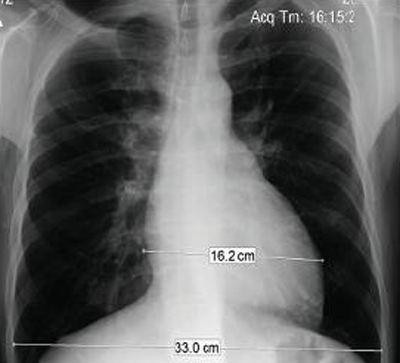

Chest x-ray in a patient with pulmonary regurgitation following repair of tetralogy of Fallot. The patient has a non-restrictive right ventricle and the heart is large

From: Chaturvedi RR, Redington AN. Heart. 2007 Jul;93(7):880-9; used with permission